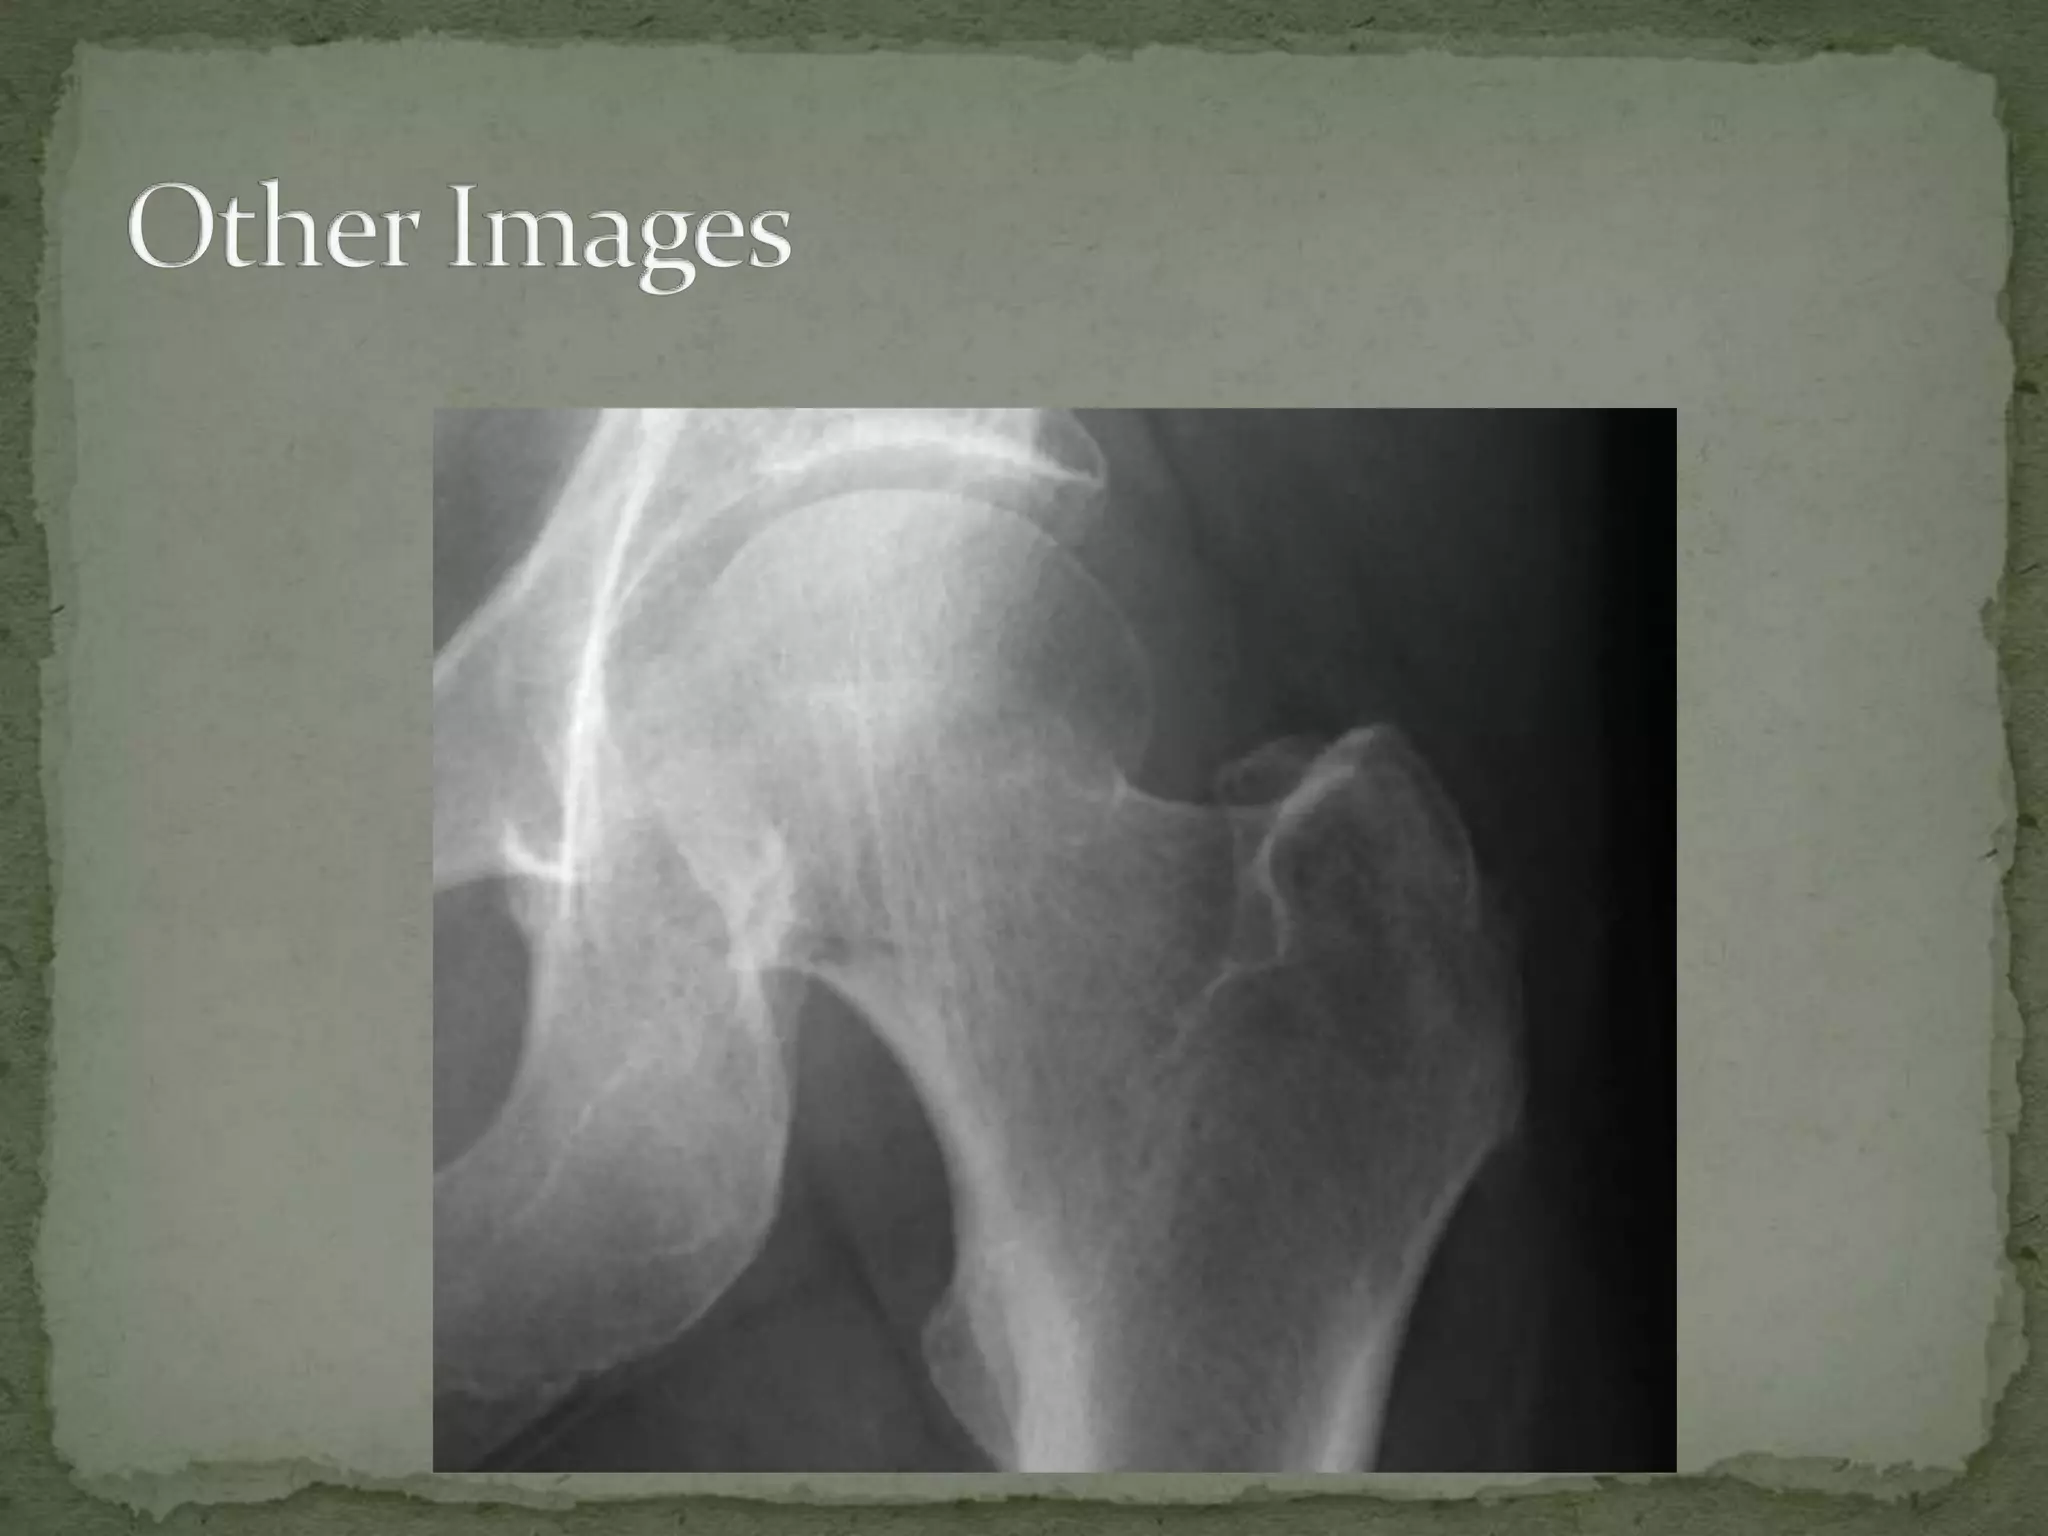

A 78-year-old woman fell at home and presented with left hip pain. On examination, her left hip was tender to touch and externally rotated and shortened, consistent with a femoral neck fracture. She will need pain control, evaluation for potential medical causes of the fall, orthopedic consultation, and operative management given the risks of increased mortality associated with delays in surgical repair for hip fractures in elderly patients.